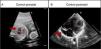

Case 1Patient aged 18 months in whom an aneurismal enlargement of the right atrium appendage was suspected prenatally, with echocardiography revealing an area of 4cm2 in the four-chamber view at 31.6 weeks’ gestational age, and no other family history of interest. The patient was born through elective caesarean delivery at 39 weeks’ gestational age and admitted for monitoring. There were no complications during labour or the perinatal period. Treatment with acetylsalicylic acid (ASA) was initiated and is still ongoing due to persistent significant enlargement. The size of the atrium has decreased gradually, with an area of 8cm2 at 4 months of chronological age and 5cm2 in the last echocardiographic control at age 18 months, which revealed no intra-auricular thrombi and a normal right atrium morphology (Fig. 1). The serial echocardiograms have not detected arrhythmias or other complications, and the patient has remained asymptomatic and with normal findings in physical examination throughout the followup.

Case 1. Right atrial appendage enlargement. (A) Foetal ultrasound at 31 weeks’ gestation, arrow points at right atrial enlargement. (B) Ultrasound: last postnatal followup at 18 months of age showing enlargement of right atrial appendage 5cm2 in diameter (arrow). AD, right atrium; AI, left atrium; VD, right ventricle; VI, left ventricle.